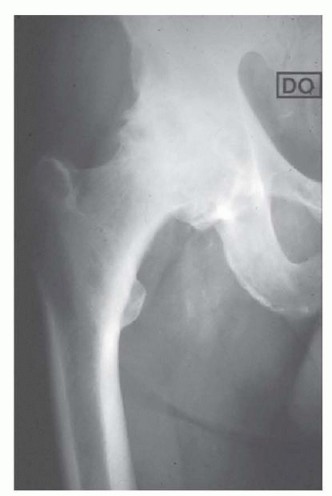

DEFINITION Hip resurfacing is a surgical procedure whereby the femoral head is preserved and a component (mos…